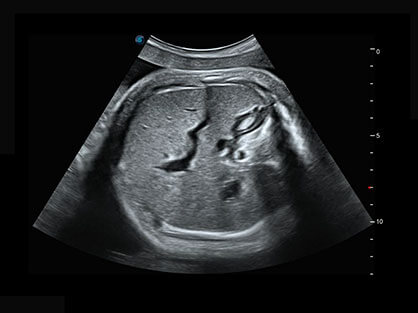

作为P系列家族成员之一,P40 Plus采用开立高端超声系统平台——极光,并以时尚秀丽、小巧灵动的外观设计绽放出灵动之韵、科技之美。高端平台的使用保证了P40 Plus优质的基础图像;完备的高级功能可满足您全身应用的基本需求;丰富的探头配置、多样的高级4D成像及分析软件为您日益增多的妇产应用需求提供丰富的诊疗方案。

结合开立超宽频带探头技术优势,能够更好地获得高分辨力与高穿透力的平衡,保证图像质量,为临床诊断保驾护航。

微米成像技术提升了对组织斑点噪声信号的抑制能力,并进一步强化边界信息,从而获得清晰图像。